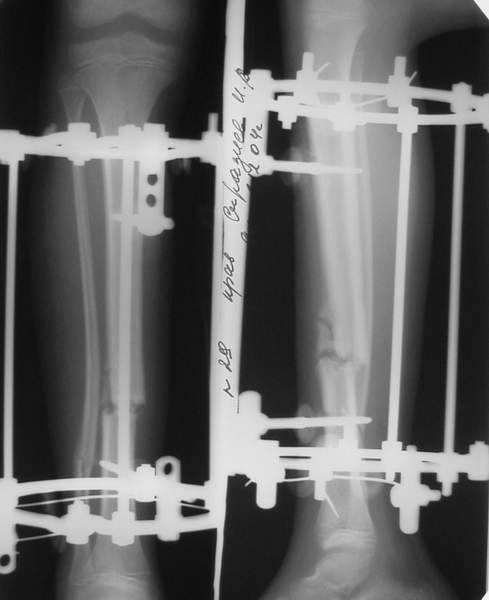

В аттачтах №№ 1 и 2 - примеры, когда 2 кольца не позволили послеоперационно

исправить смещение фрагментов большеберцовой (по ширине и вальгусное).

А казалось бы (#2) - поиграй на штангах и все влетит.

Оперировал не я

1

1a